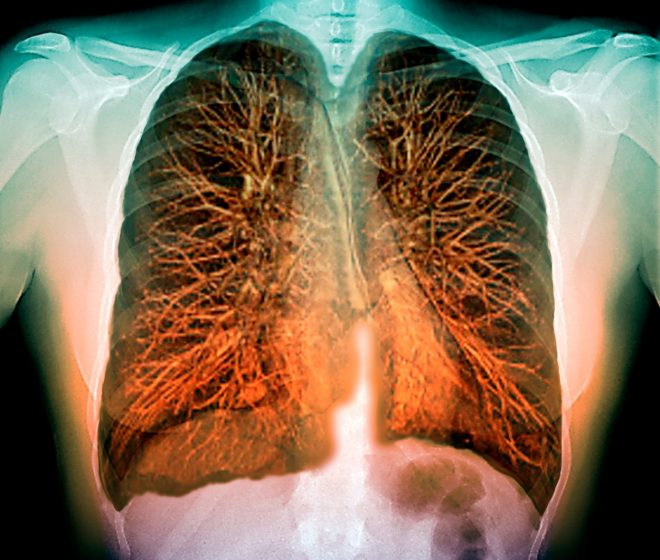

Vejpanje oz. uporaba elektronskih cigaret škodljivo za dihala

Ameriški bolniki poročajo o postopnem pojavu kašlja, težav pri dihanju in utrujenosti, ki so se poslabšali v času nekaj dni ali tednov. Poročajo tudi o drugih težavah, kot so zvišana telesna temperatura, bolečine v prsih, izguba telesne teže, slabost in driska. Slikanja pljuč prikazujejo zgostitve v obeh pljučnih krilih, strokovnjaki pa so potrdili, da ne gre za nalezljivo bolezen.

Trenutno ni identificiran posamezni izdelek ali snov oz. vzrok obolenj, vendar pa oboleli poročajo o uporabi elektronskih cigaret v tednih in mesecih pred sprejemom v bolnišnico. Na NIJZ zato zdravstvenim delavcem svetujejo, naj pri obravnavi bolnikov z respiratornimi oziroma pljučnimi obolenji neznanega vzroka preverijo tudi uporabo elektronskih cigaret oziroma drugih dovoljenih in prepovedanih drog.